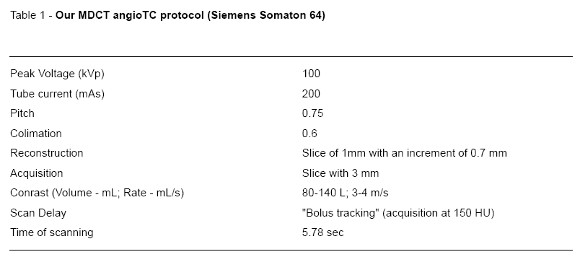

- The past few years have seen decisive dynamic developments in CT technology, mainly brought about by the advent of multi–detector row CT. The current generation of four–, eight–, and 16– and 64-detector row CT scanners now allow for coverage of the entire chest with 1-mm or submillimeter resolution within a short single breath-holdnow less than 6 seconds in the case of a 64–detector row CT, as it is in our institution. The protocol we use is according to the literature (Table 1).

Complete Obstruction

On pulmonary angiograms,the diagnostic sign ofacute PE with complete obstruction is a concave filling defect or trailing edge that should be seen within the contrast material at thelevel of the obstruction.CTis able to show thrombus distal to the obstruction that cannot be seen on an angiogram. At the site of the thrombus, the diameter of the pulmonary artery may be increased because of impaction of the thrombus by pulsatile flow (Fig.1).